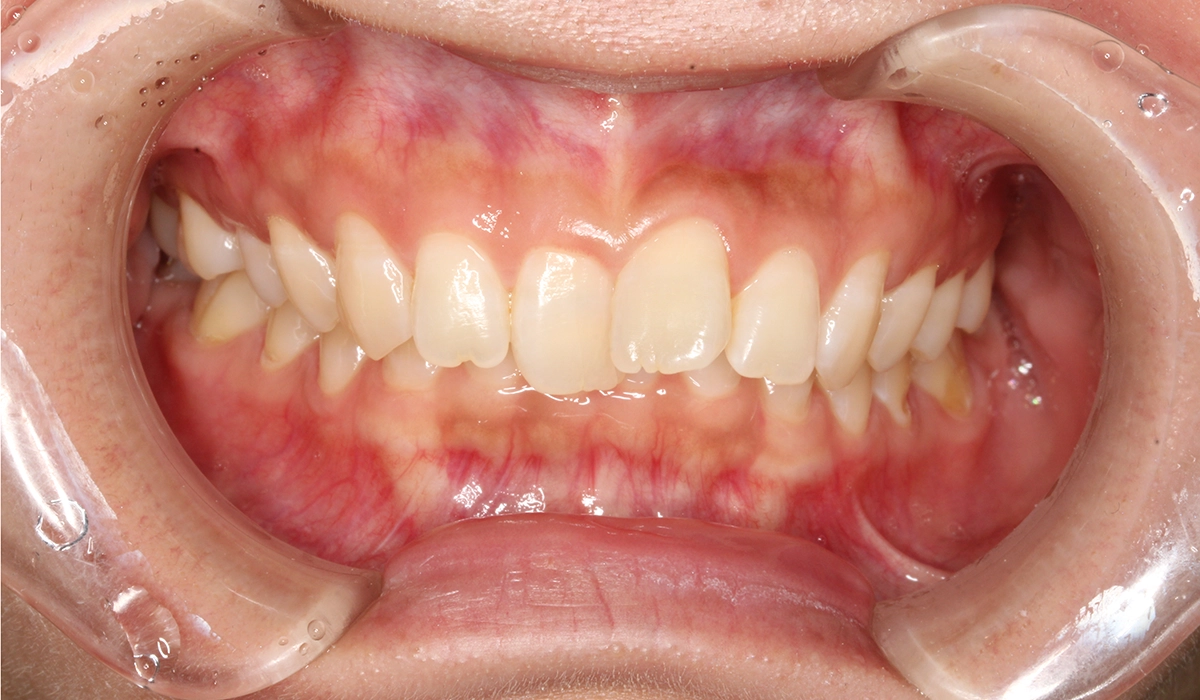

術前:正面

術後:正面